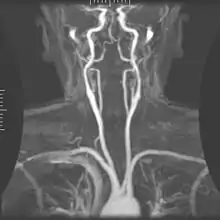

Angiografia

A angiografia por ressonância magnética (MRA) gera imagens das artérias para avaliá-las para estenose (estreitamento anormal) ou aneurismas (dilatação da parede vascular, em risco de ruptura). O MRA é frequentemente usado para avaliar as artérias do pescoço e do cérebro, a aorta torácica e abdominal, as artérias renais e as pernas (chamado de "escorrer"). Uma variedade de técnicas podem ser usadas para gerar as imagens, como a administração de um agente de contraste paramagnético (gadolínio) ou usando uma técnica conhecida como "aprimoramento relacionado ao fluxo" (por exemplo, sequências de tempo de voo 2D e 3D), onde a maior parte do sinal em uma imagem é devido ao sangue que recentemente se mudou para esse plano. As técnicas que envolvem acumulação de fase (conhecida como angiografia por contraste de fase) também podem ser usadas para gerar mapas de velocidade de fluxo com facilidade e precisão. A venografia por ressonância magnética (MRV) é um procedimento similar que é usado para imagens de veias. Neste método, o tecido agora está excitado inferiormente, enquanto o sinal é recolhido no plano imediatamente superior ao plano de excitação - criando assim o sangue venoso que recentemente se moveu do plano excitado.[49]

| Angiografia e venografia por Ressonância Magnética (MRA) | Voo de tempo | TOF | O sangue que entra na área de imagem ainda não está saturado magneticamente, dando um sinal muito mais alto ao usar tempo de eco curto e compensação de fluxo. | Detecção de aneurisma, estenose ou dissecção.[86] | ![]() |